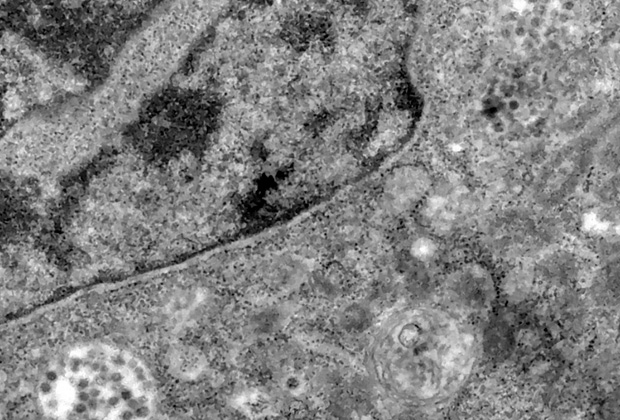

Бразильским ученым удалось зафиксировать на фотографиях момент заражения клетки коронавирусом. Снимки были опубликованы на сайте Фонда Освальдо Круз (Бразилия).

Ученые утверждают, что на снимках можно увидеть момент, когда вирус SARS-CoV-2 проникает в клетку и заражает ее. На изображениях заметны темные точки, которые проникают в цитоплазму клетки, внутри которой расположено ее ядро с генетическим материалом. Финальный снимок содержит скопление частиц возбудителя инфекции в инфицированной клетке.

Фотографии были выполнены с помощью электронного микроскопа, способного увеличивать объекты до двух миллионов раз. По словам специалистов, снимки были сделаны случайно во время изучения репликации вируса. Фонд уточнил, что изображенные на фото клетки принадлежат не человеку, а примату из вида зеленых мартышек, генетический материал которых часто используется в научных целях.